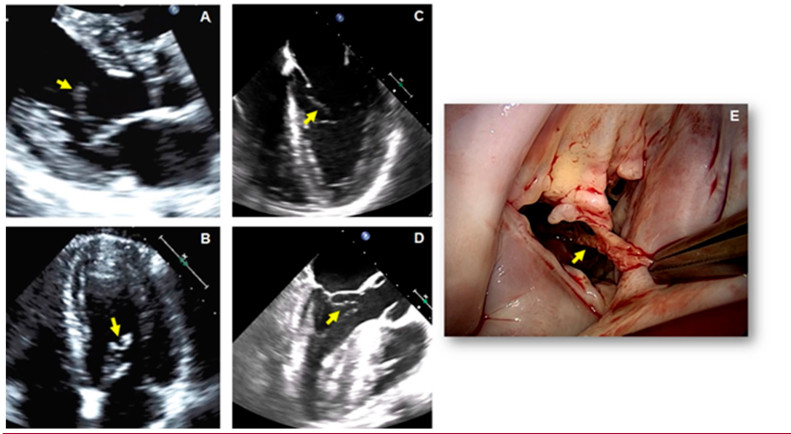

Un hombre de 38 años sin antecedentes médicos presentó dos episodios transitorios de debilidad del brazo y la pierna derechos 48 horas antes del ingreso hospitalario. La tomografía cerebral y la resonancia magnética arrojaron resultados negativos, y en la ecografía Doppler de las carótidas no se apreciaron anomalías. En el electrocardiograma se observó ritmo sinusal normal sin alteraciones. Se realizaron un ETT y posteriormente un ETE.

En las vistas en eje largo paraesternal y apical de 4 cámaras del ETT se observa una estructura ecodensa, delgada y con mucha movilidad adherida a la cara ventricular de la valva anterior de la VM (Figs. 3A y B respectivamente, flechas amarillas). Esto también se visualiza en las imágenes del ETE, según la vista medioesofágica de 4 cámaras (Fig. 3C, flecha amarilla) y de 3 cámaras donde se puede observar que esta estructura es arrastrada hacia el infundíbulo del ventrículo izquierdo durante la sístole (Fig.3D, flecha amarilla). En las imágenes obtenidas durante la resección quirúrgica del tumor, se muestra muy buena correlación con los hallazgos ecocardiográficos, en cuanto a las características anatómicas y la localización (Fig. 3E). El estudio de anatomía patológica determinó el diagnóstico de fibroelastoma papilar (FEP) de la VM.

Objetivos de aprendizaje: El FEP es el tercer tumor más frecuente del corazón después del mixoma y el lipoma auriculares, y es el tumor más habitual en las válvulas cardíacas. 8 En el 90% de los casos, los FEP son únicos y más del 95% se localizan en el corazón izquierdo. 8 Aunque histológicamente sea benigno, el FEP es una afección peligrosa debido a la posibilidad de embolización cerebral y coronaria. 9 Las dos terceras partes de los casos se diagnostican de forma fortuita mediante un ETT sistemática, y una tercera parte se diagnostica después de un evento embólico que desencadena la exploración. 9 Se recomienda su extirpación para evitar complicaciones embólicas; esto constituye el tratamiento definitivo, ya que la recidiva es muy poco frecuente. 8